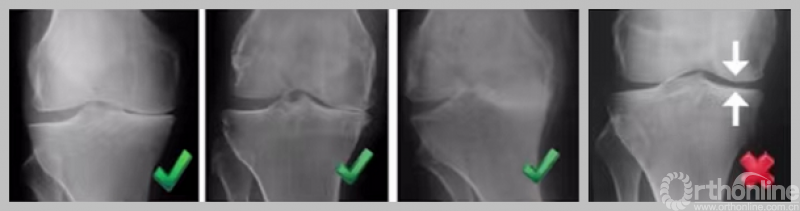

1. 内侧骨关节炎

a.病变位于内侧平台中线以前;b.病变超过平台中线;c.病变触及平台后缘

2. 骨对骨表现

负重位;内翻应力位。

3. 外侧全层软骨完好

负重位及外翻应力位保证外侧间隙正常。

4. MCL功能正常

可复性关节内畸形,屈曲20°,外翻应力位X线片。